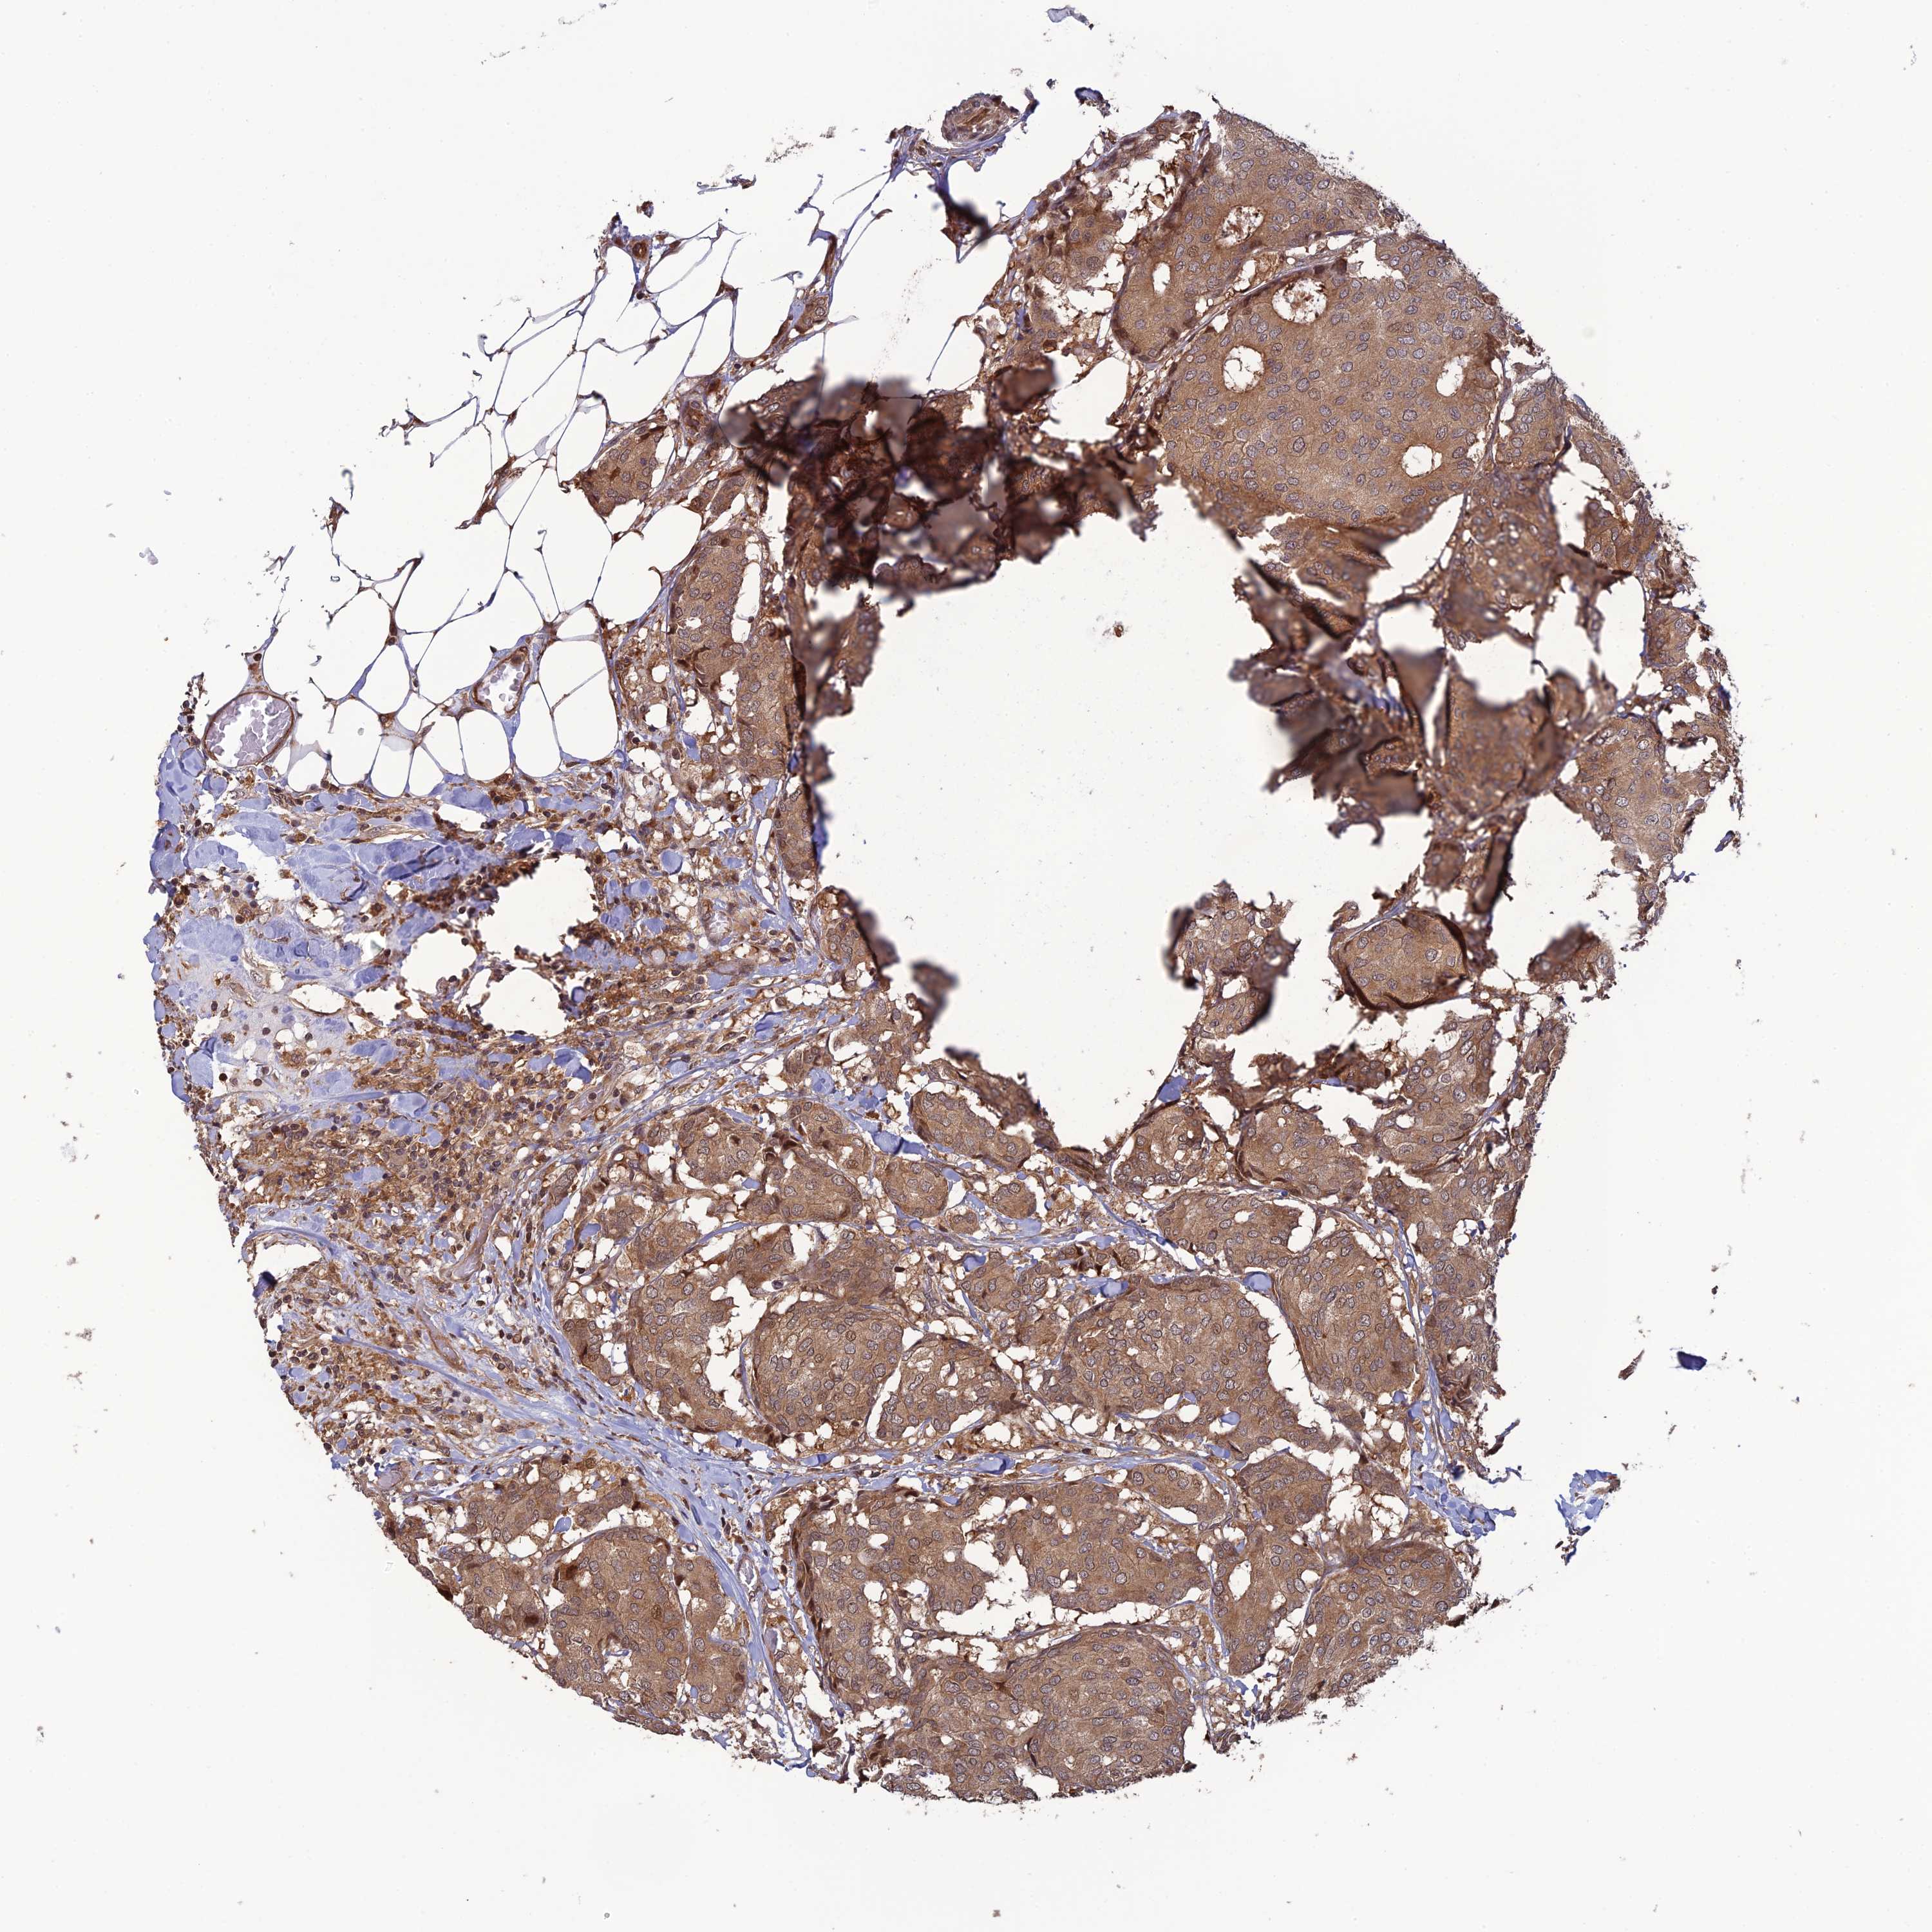

BRCA TCGA BRCA VALIDATION PROTEIN EXPRESSION

ANTIBODIES

AND

VALIDATION